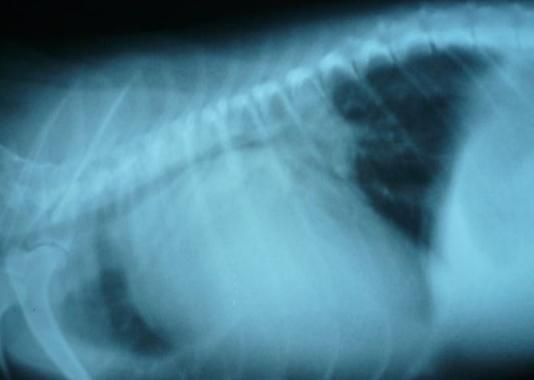

二、兽用DR的成像速度快,采集时间10ms以下,成像时间仅为3秒,放射诊断医师即刻在屏幕上观察图像。数秒即可传送至后处理工作站,进行阅片处理诊断报告,常规胸部DR照片从检查到出诊断报告大约5—10分钟。

三、兽用DR有较高的空间分辨力和低噪声率,非晶硅接受X线照射后直接转换为电信号,可避免其他成像方式如普通屏片组合照片、CR等光照射磷物质后散射引起的图像锐利度减低,因此可获得高清晰图像。提高了病灶的检出率,避免漏诊误诊等问题。

3、曝光时间。一般对于胸部X线检查,尤其是呼吸急促病患的检查,曝光时间太长会导致运动伪影,从而引起图像边缘不清晰。通常要求的曝光时间短能达到0.04s即可,这个曝光时间下,即使呼吸急促的病患检查,也一般不会产生肉眼明显可见的运动伪影;